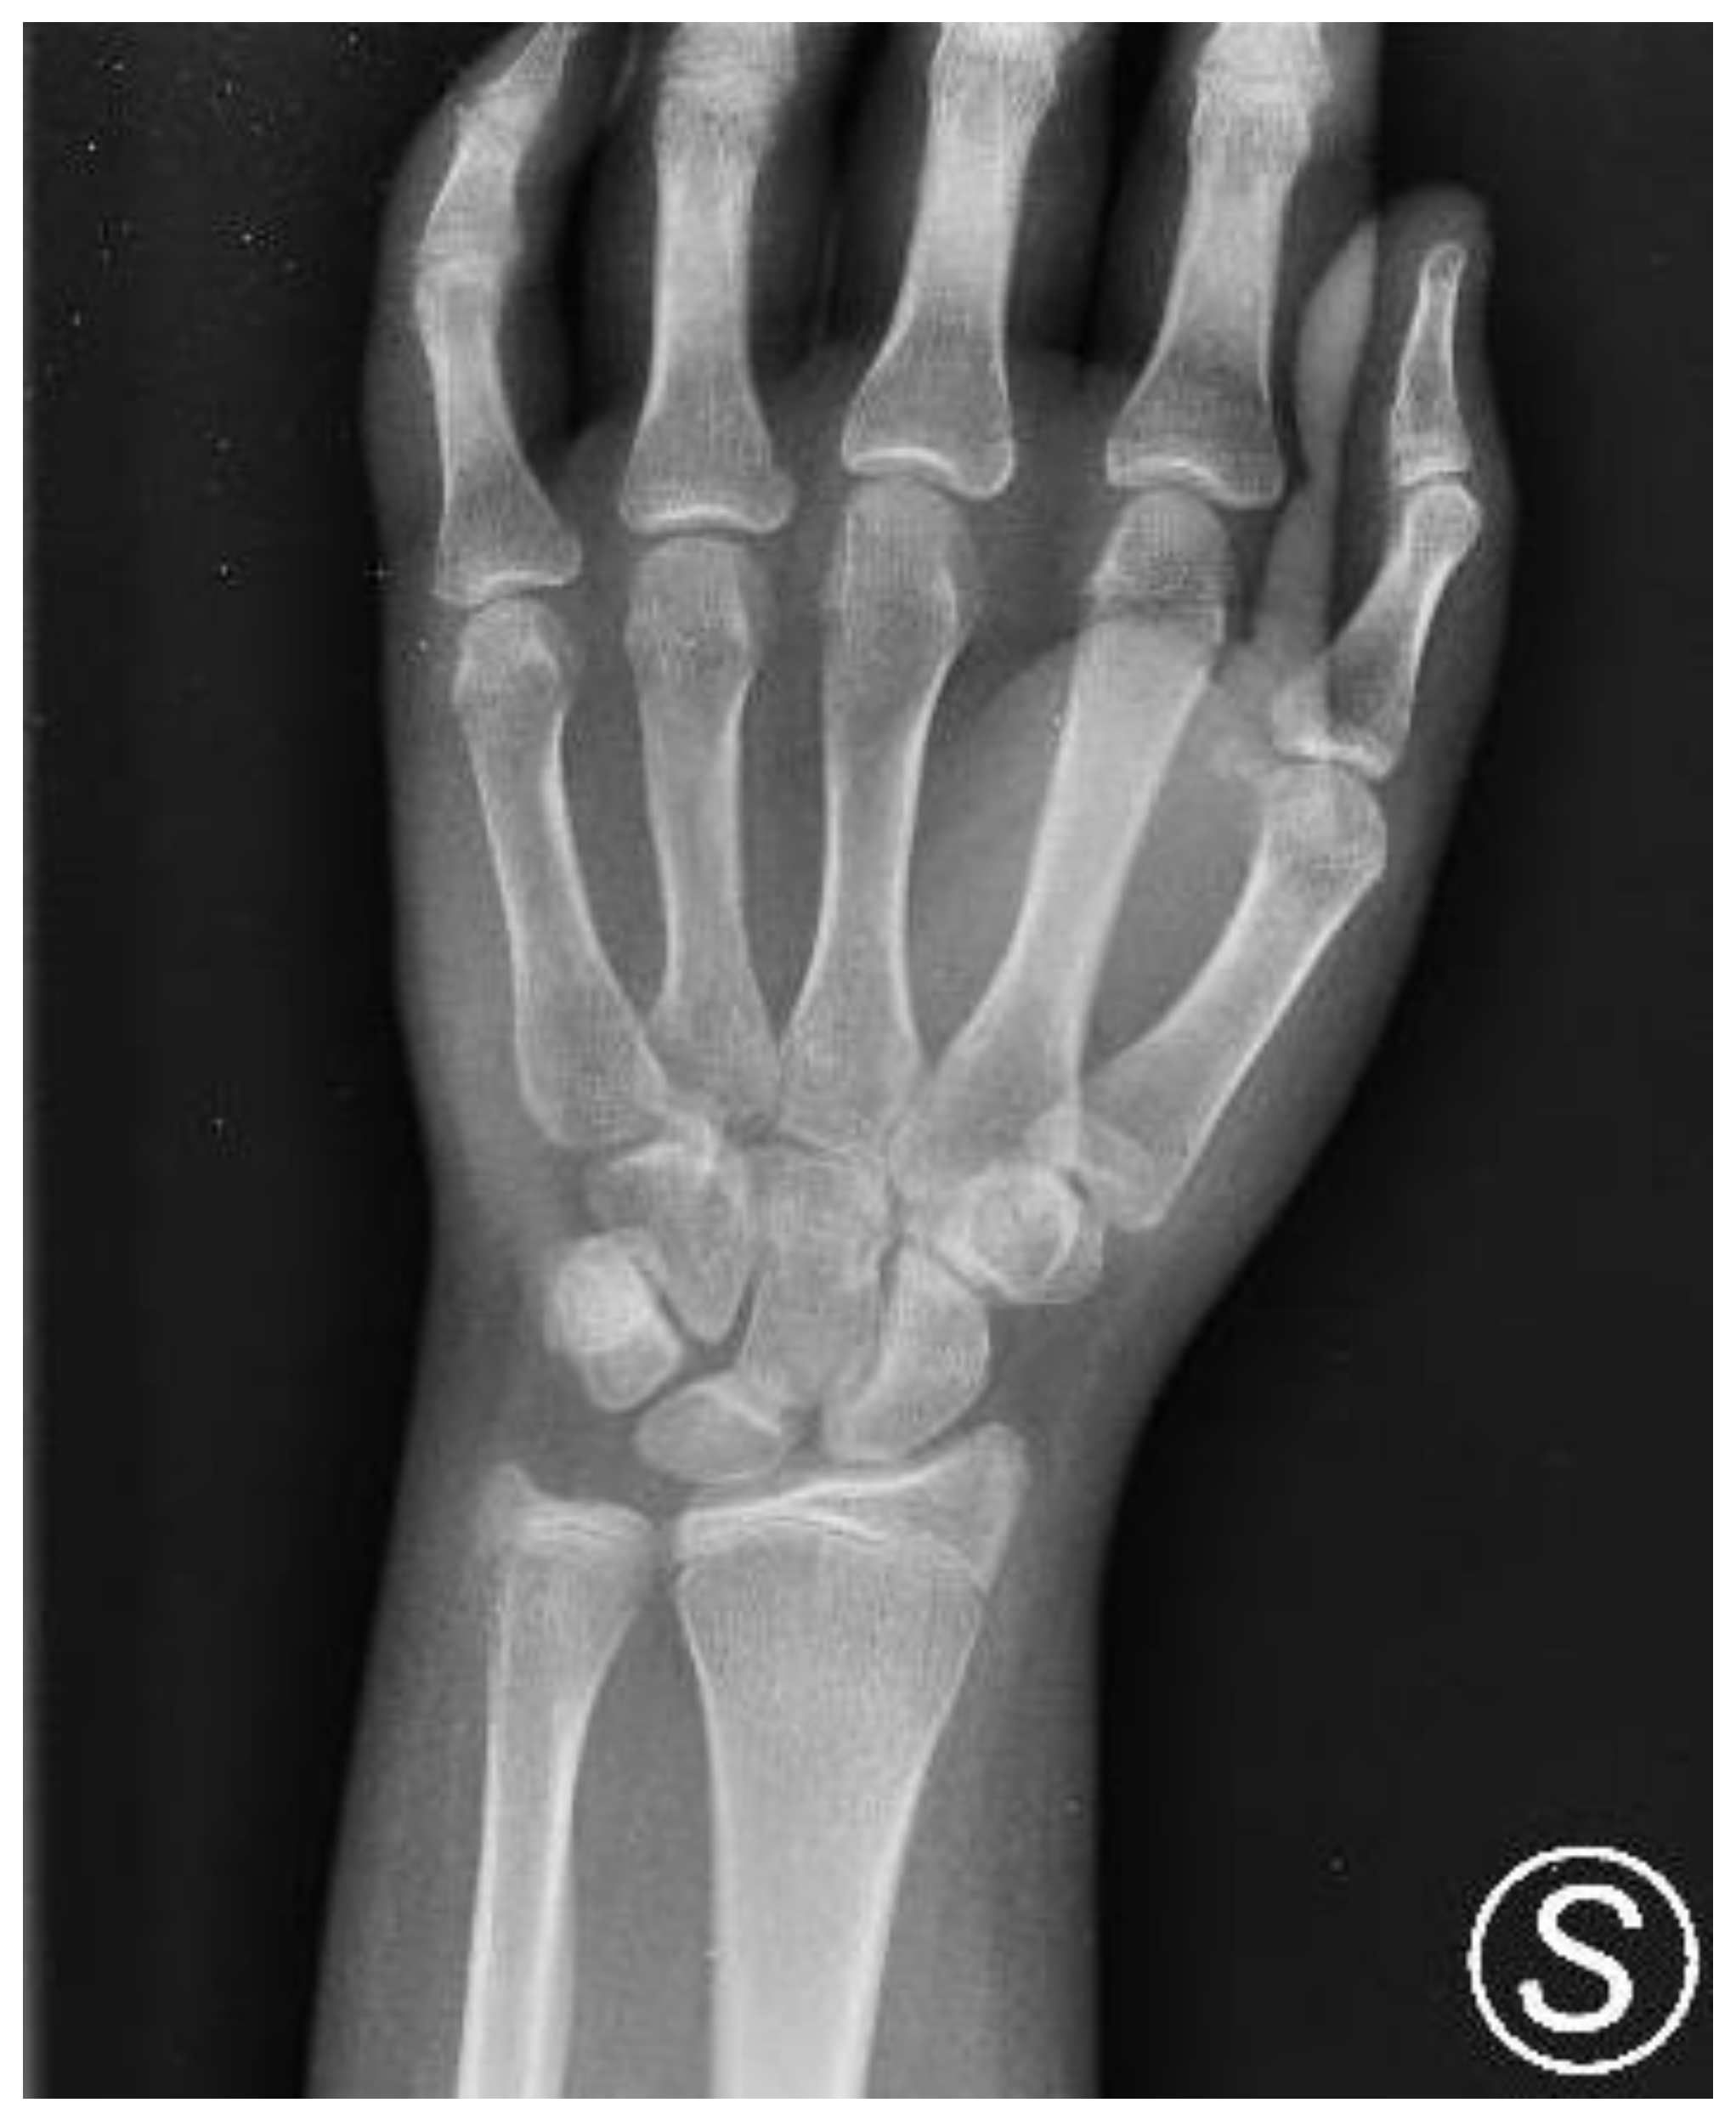

2. Case Presentation

2.1. Evaluation